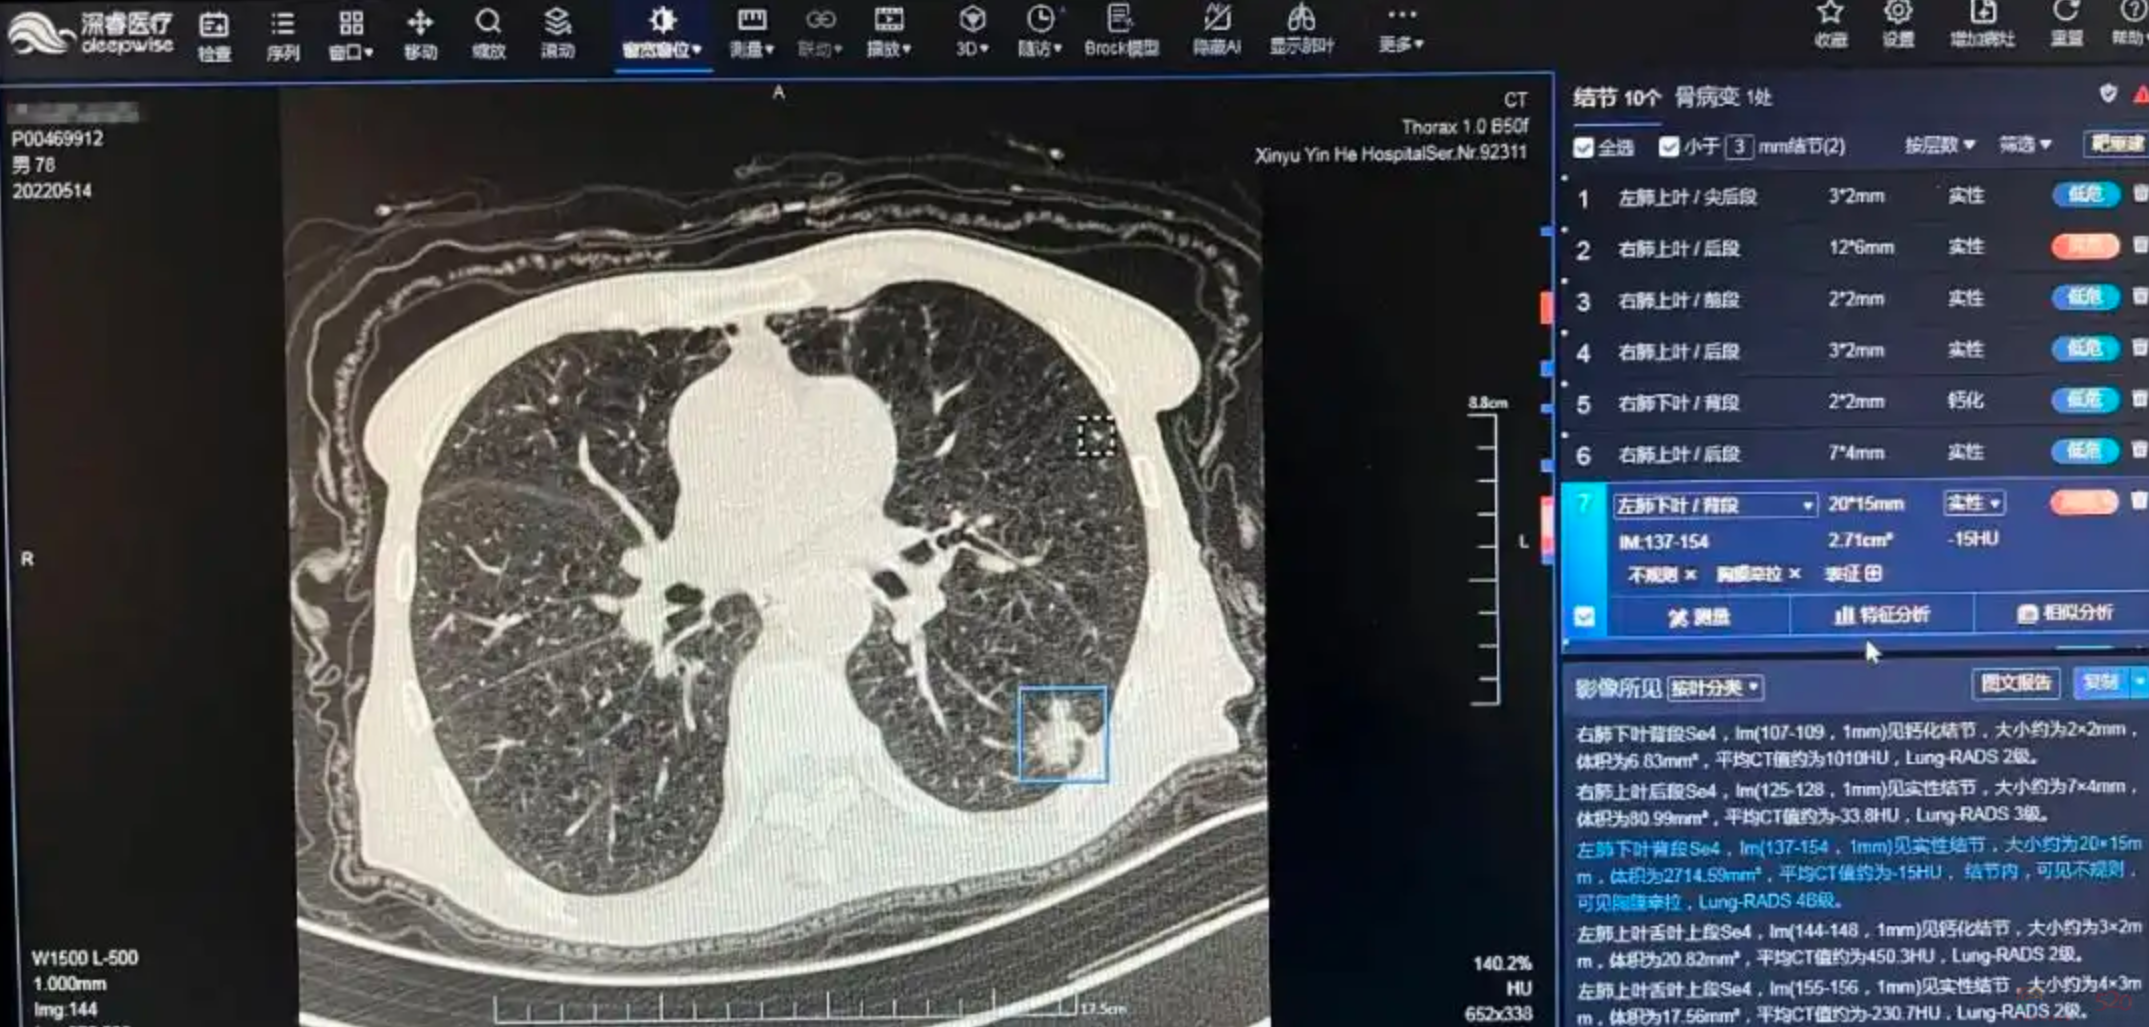

如今有些医院引入了肺结节AI筛查的技术,用AI筛查胸片、便于观测出人眼可能错过的小结节。

这也会让结节的检出率有所提升。